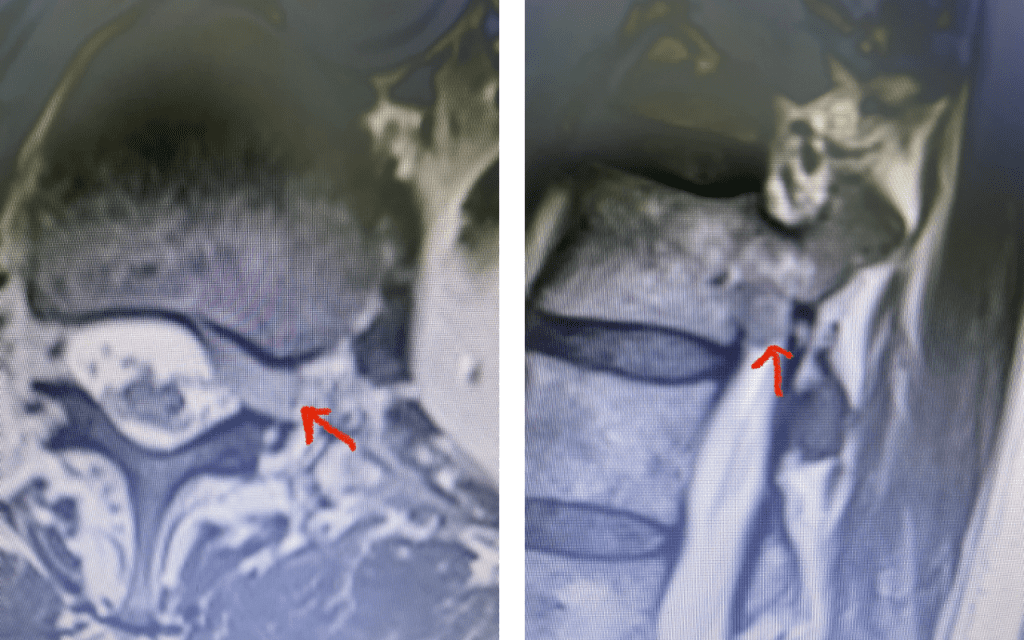

As an example of this type of pain syndrome, an interesting 58-year-old female presented with “soreness” and numbness of her left groin area for 6 months. She had no leg or back pain, weakness, or bowel or bladder dysfunction. She sought gynecological care, for which she had a pelvic examination. The examination elicited pain on left-sided palpation. She had negative imaging of her pelvis. Her family physician ordered a lumbar MRI, which revealed a left foraminal disc herniation compressing the left L1 root superiorly against the L1 pedicle (Fig 4). Clearly the numbness was in an L1 dermatomal distribution and correlated with the patient’s MRI. We started the patient on Medrol and Neurontin. We referred her to pain management for a left L1-2 transforaminal epidural and will follow her up in 6 weeks. If her problem does not resolve, we will offer surgical removal. It is important to realize that many patients with spinal pathology can present pain syndromes that mimic other conditions. For example, a patient may have an upper thoracic compression fracture with pain referred to the anterior chest wall, which can cause the patient to feel like they are having a heart attack. It is only during a cardiac workup that they discover the underlying problem with a chest x-ray.

Fig 4: Axial and Sagittal T2-weighted lumbar MRI demonstrating a left lateral foraminal disc herniation (red arrow) causing compression of the exiting L1 nerve root against the undersurface of the pedicle of L1.